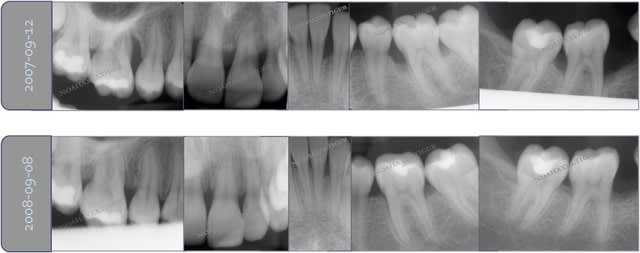

Puique vous avez l'air de douter Olivier et toi sur ce qui est pour moi une base enseignée à la fac en cycle commun, je vous poste 2 cas avant après pose du biomat (résultat à 2 et 4 mois) Désolé de la piètre qualité de la radio avant elle provient d'un zoom du BLC initial photographié.

37 avant sgtutm - Eugenol

37 apr s fktiho - Eugenol

46 avant tpineb - Eugenol

46 apr s p2okx4 - Eugenol

Je précise que dans les 2 cas c'est du Novabone et que je n'ai pas eu besoin d'utiliser de membrane (c'est un matériau putty qui se place très bien)